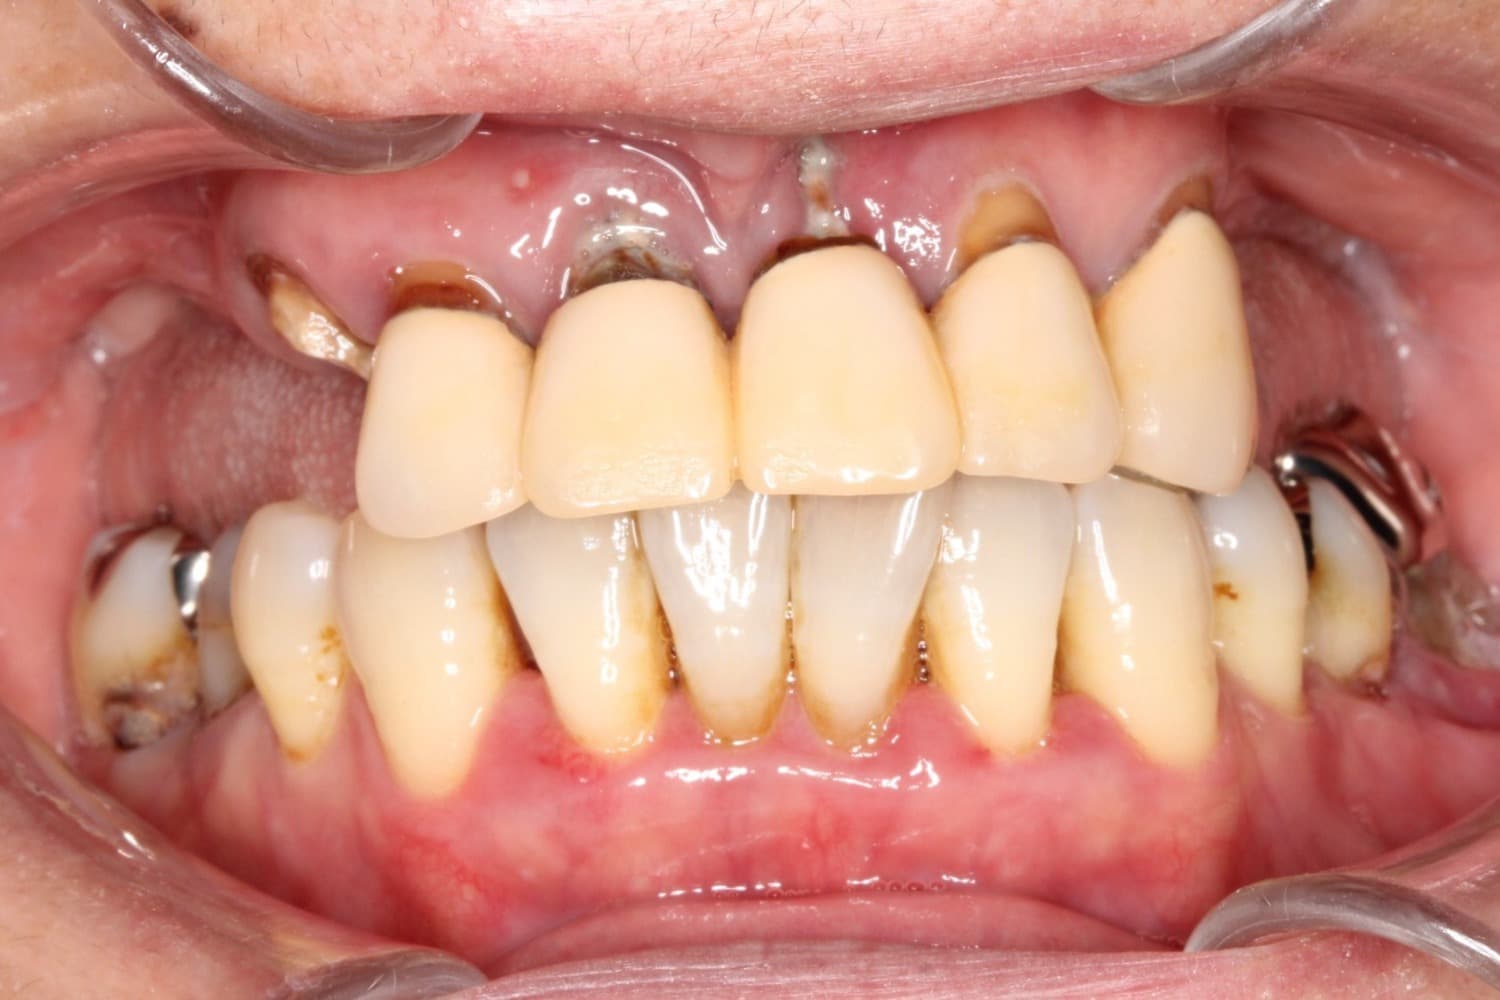

上顎のインプラント治療

Before

After

上顎全ての歯が保存不可能。5本のインプラント埋入を行いました。 費用や清掃性を考慮し、短縮歯列での治療としました。 治療後は見た目も満足され、何でも食べることが出来ると、患者様も非常に喜ばれています。

年齢

60代

性別

女性

主訴

しっかり咬めるようになりたい。見た目も綺麗にしたい。

治療期間

6ヵ月

治療回数

12回

費用

上顎全て:約300万円

副作用・リスク

術後の腫れや痛みの可能性、インプラントの骨結合不良、清掃不良による治癒不全